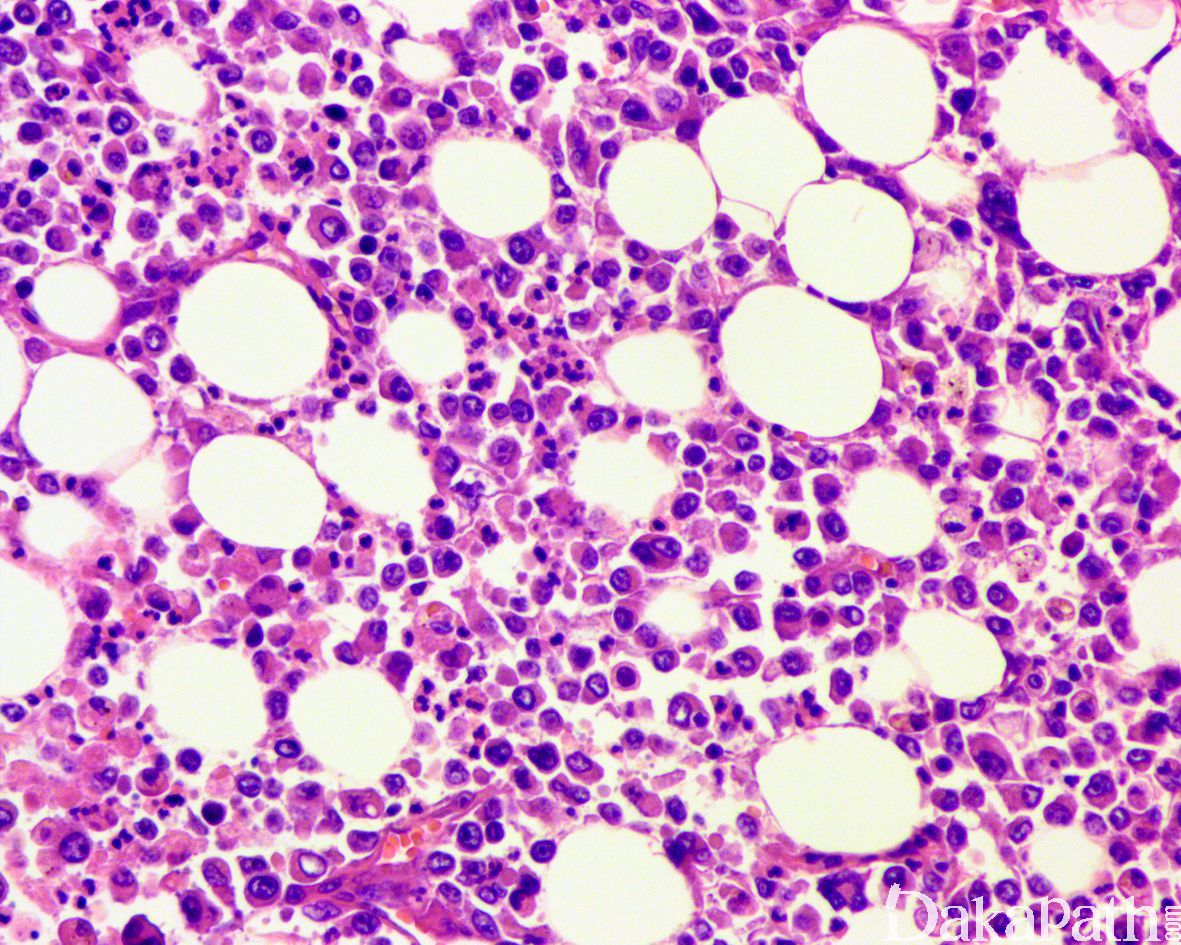

组织学表现为在疏松或黏液样间质中出现弥漫性排列的单个肿瘤细胞;

肿瘤细胞胞质透亮或嗜酸性,核大、中位或偏位,具有小核仁,似浆细胞或淋巴细胞,多形性不明显;

少数病例肿瘤细胞似印戒细胞,但与细胞外黏液无关,也称为印戒细胞样尿路上皮癌; 5.50%病例可找到高级别的普通型浸润性尿路上皮癌成分;